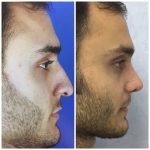

– متخصص جراحی فک , پلاستیک صورت و بینی

جراحی فک , پلاستیک , صورت وبینی

جراحی ترمیمی و زیبایی فک و صورت و جمجمه و گردن